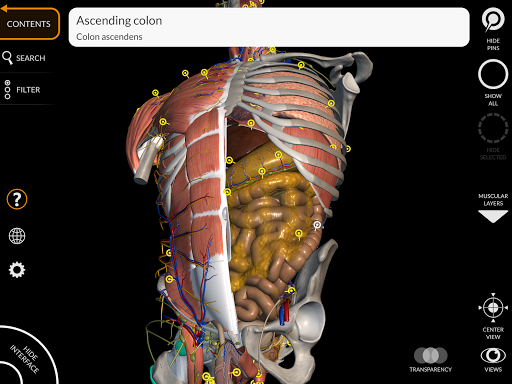

La subdivision par régions et les vues prédéfinies facilitent l'observation et l'étude de parties individuelles ou de groupes de systèmes et les relations entre différents organes.

• Système digestif

• Fonction de recherche pour trouver facilement chaque partie anatomique

• En sélectionnant un modèle ou une épingle, le terme anatomique associé apparaît